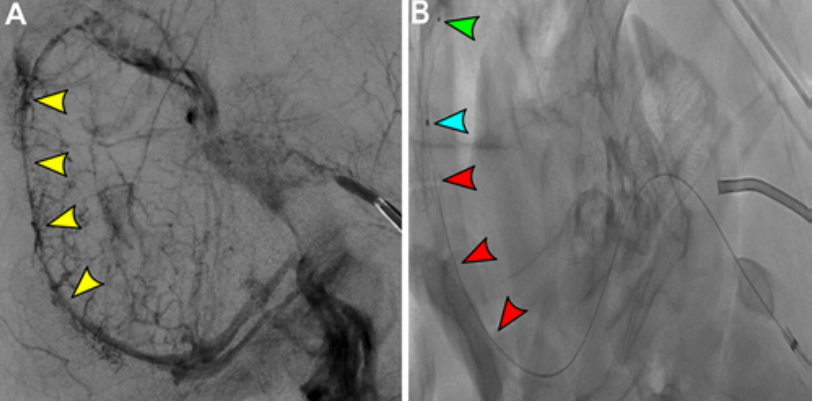

一种用于测试颅内静脉窦血栓机械取栓和血管内成像的临床前模型

图片尺寸813x402

图片尺寸1080x402